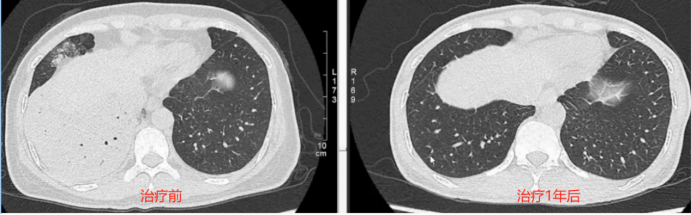

最终确诊:肺腺癌,ROS1阳性。克唑替尼治疗1年复查,两肺病灶基本吸收(图3)

图片

3  患者治疗前后胸部CT对比